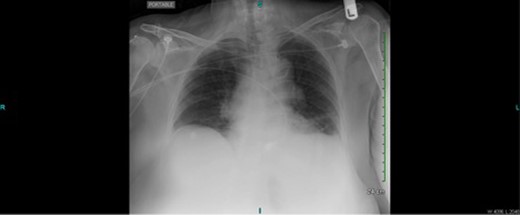

She complained of shortness of breath and chest pain. Vital signs were notable for pulse of 110/min, blood pressure 110/70 mmHg, respiratory rate of 20/min. On physical examination, she appeared uncomfortable, diaphoretic and pale. The abdominal exam was benign. Laboratory work-up was remarkable for haemoglobin of 8.5 mg/dl (preoperative hemoglobin was 9.5 mg/dl). Given her prior history of coronary artery disease, she underwent an electrocardiogram and serum troponin levels were normal. A portable upright chest X-ray was found to be negative for pneumoperitoneum, effusions or infiltrates (Fig. 1).

Upright portable chest X-ray without evidence of pneumoperitoneum, effusions or infiltrates.